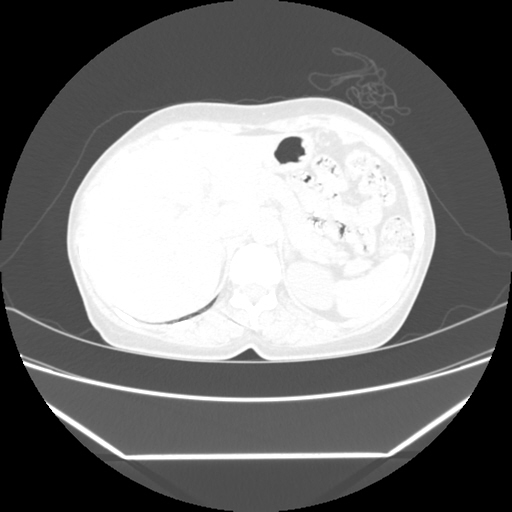

Radiological images:

HRCT is also done on 13/11/15